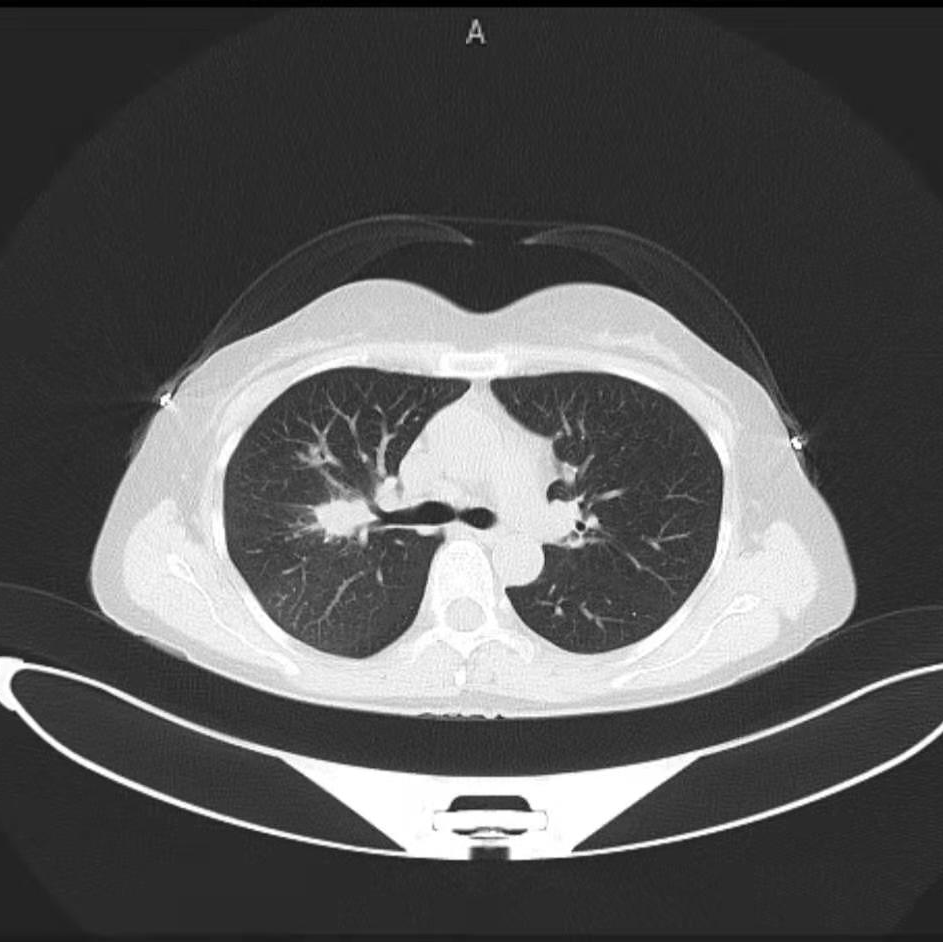

2019年8月(51岁),来院检测CT示肺部阴影,PET-CT示高代谢病灶。行超声支纤镜活检示:低分化鳞癌。

图2:2019年8月23日CT及PET-CT结果

CT: 2019/8/23

(靶向治疗前)

CT: 2019/11/2

(靶向治疗1个半月)